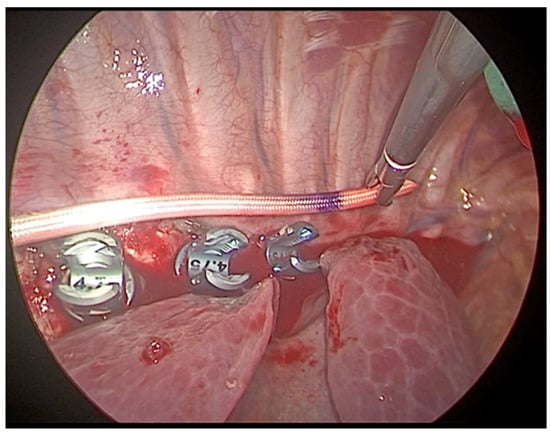

2.2.2. Surgical Technique

- Adequate trocars positioning is essential in order to correctly place the screws in the vertebral bodies. Fluoroscopy use in anterior and lateral view guides the orthopedist to the correct insertion.

- A correct interaction between pediatric and orthopedic surgeon, integrated by the combined use of thoracoscopic visualization and fluoroscopy, allow the orthopedist to correctly position the devices at the level of the vertebrae to be treated.